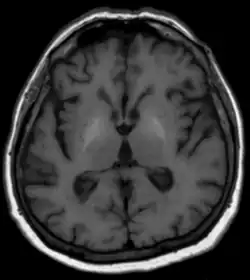

Für die Diagnostik der zugrunde liegenden Lebererkrankung stehen die üblichen Methoden der Blutuntersuchungen, Sonographie und anderer Schnittbildverfahren sowie die Klinik und gegebenenfalls eine Gewebeprobe der Leber mit histologischer Untersuchung zur Verfügung. Bezüglich der Degeneration im Gehirn sind in der Computertomographie meist keine Veränderungen zu erkennen. Die MRT zeigt typischerweise in den Basalganglien in T1-gewichteten nativen Sequenzen eine Signalerhöhung. Als Ursache werden Ablagerungen von paramagnetischen Mineralien vermutet, die nach Lebertransplantation auch reversibel sein können. T2-gewichtete Aufnahmen zeigen meist keine Auffälligkeiten. Differentialdiagnostisch werden die oben beschriebenen Signalveränderungen gelegentlich bei langer parenteraler Ernährung aber auch bei idiopathischen Verkalkungen gesehen. Auch ein Morbus Wilson ist differentialdiagnostisch in Erwägung zu ziehen.